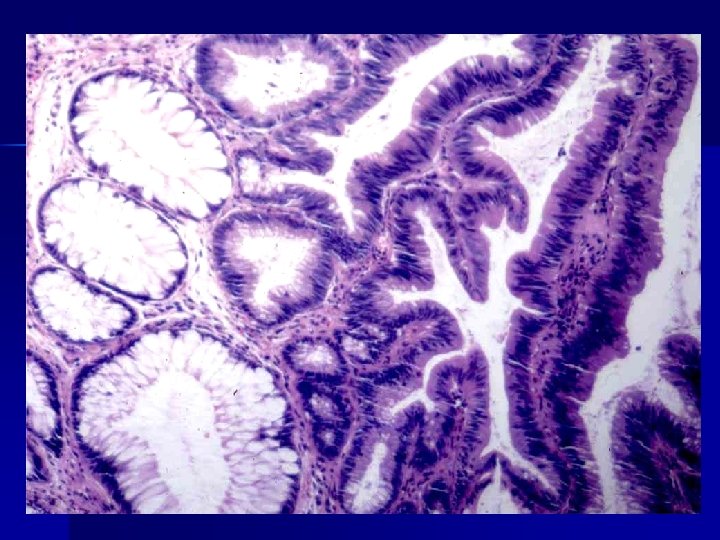

METAPLASIA

METAPLASIA n n Es una alteración reversible en la que un tipo celular maduro es sustituido por otro (epitelial o mesenquimatoso) Ejemplos: metaplasia escamosa, Esófago de Barret. Los fibroblastos pueden transformarse en osteoblastos o condroblastos. Existe una reprogramación genética en las células mesenquimatosas indiferenciadas de los epitelios por citocinas, factores de crecimiento.

1. Metaplasias epiteliales: Metaplasia epitelial escamosa: mucosas, conductos, bronquios, cervix, endometrio y próstata. Metaplasia epitelial apocrina: glándulas exocrinas de la mama. Metaplasia intestinal: En las gastritis y colecistitis crónicas y esófago de Barrett. Metaplasia antral: En la vesícula biliar y cuerpo gástrico.